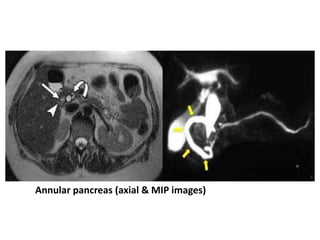

Annular pancreas

• Is a morphological anomaly that results in pancreatic tissue completely

Annular pancreas (axial & MIP images)